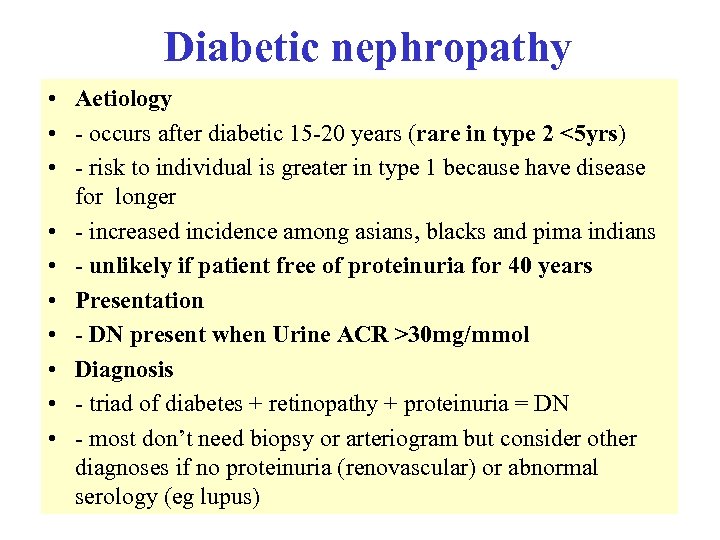

Diabetic nephropathy • Aetiology • - occurs after diabetic 15 -20 years (rare in type 2 <5 yrs) • - risk to individual is greater in type 1 because have disease for longer • - increased incidence among asians, blacks and pima indians • - unlikely if patient free of proteinuria for 40 years • Presentation • - DN present when Urine ACR >30 mg/mmol • Diagnosis • - triad of diabetes + retinopathy + proteinuria = DN • - most don’t need biopsy or arteriogram but consider other diagnoses if no proteinuria (renovascular) or abnormal serology (eg lupus)

Diabetic nephropathy • Aetiology • - occurs after diabetic 15 -20 years (rare in type 2 <5 yrs) • - risk to individual is greater in type 1 because have disease for longer • - increased incidence among asians, blacks and pima indians • - unlikely if patient free of proteinuria for 40 years • Presentation • - DN present when Urine ACR >30 mg/mmol • Diagnosis • - triad of diabetes + retinopathy + proteinuria = DN • - most don’t need biopsy or arteriogram but consider other diagnoses if no proteinuria (renovascular) or abnormal serology (eg lupus)